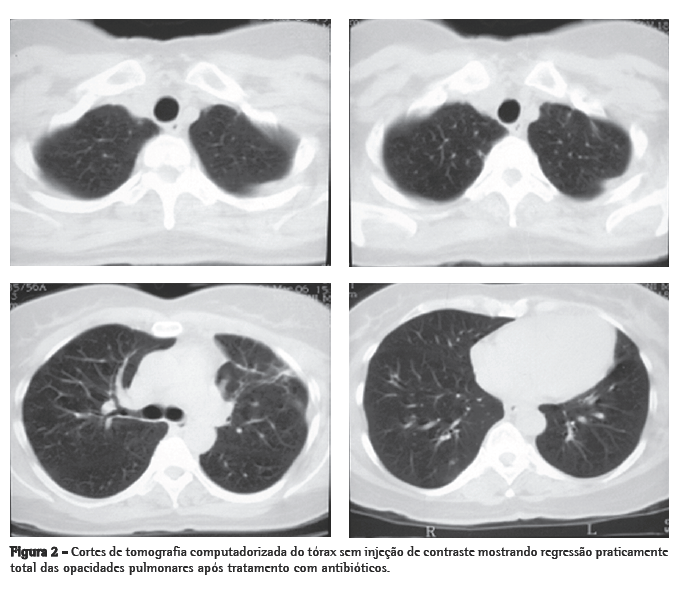

A tomografia computadorizada de tórax de controle após este curso de antibióticos mostrou regressão praticamente total das opacidades (Figura 2). Permaneceu afebril desde o terceiro dia do novo curso de antibióticos. Nenhum microrganismo foi isolado das hemoculturas e culturas do lavado broncoalveolar. A anticoagulação foi suspensa após 20 dias de uso, pela falta de evidência de benefício na síndrome de Lemierre.